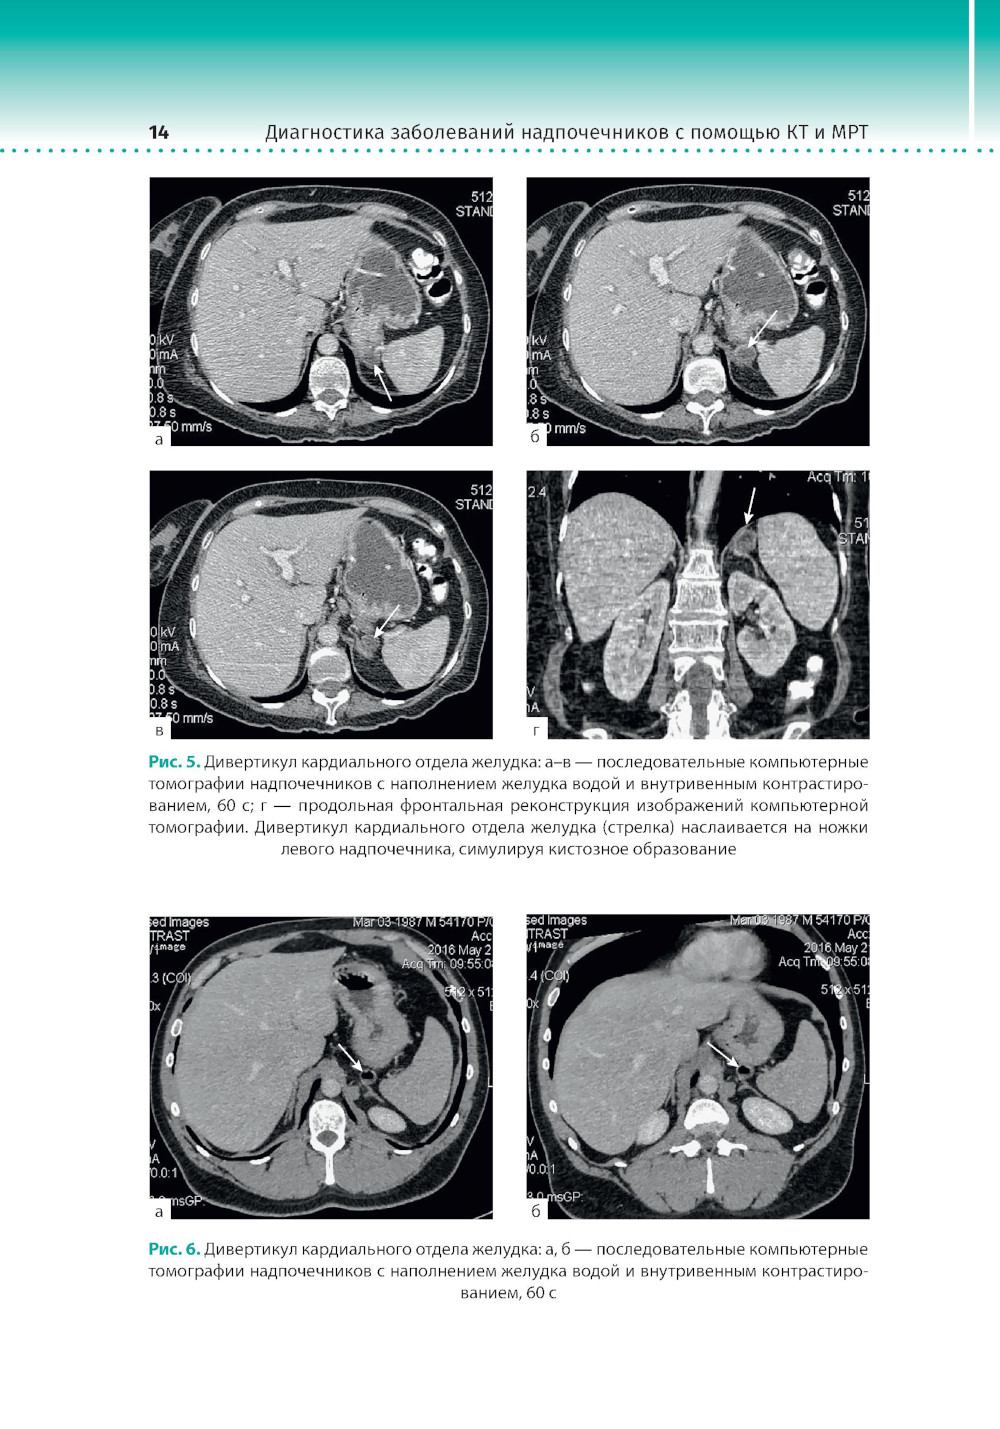

Диагностика заболеваний надпочечников с помощью КТ и МРТ